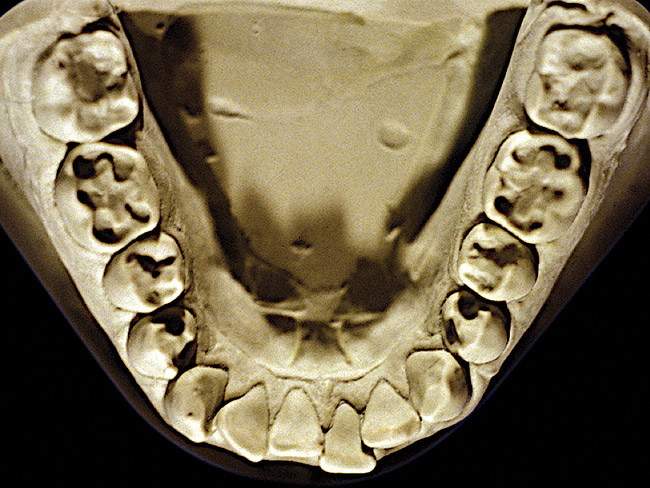

Figure 2  Advanced NCLTS from bruxism, mandibular arch.

Figure 2

The patient shown in Figure 3 and Figure 4 exhibited severe NCLTS from bruxism. Examination of the casts indicated that the NCLTS was progressively greater toward the anterior teeth. Cupping and cratering was not present because there was no secondary cause. Figure 5 and Figure 6 detail another bruxism patient, but to a lesser degree and one with cupping/cratering caused by toothpaste. The cups or craters were not caused from bruxism because the teeth could not touch the bottom of the invaginations. In both featured patients, upon hand-articulating the casts, the NCLTS facets matched up and the diagnosis of bruxism was confirmed.